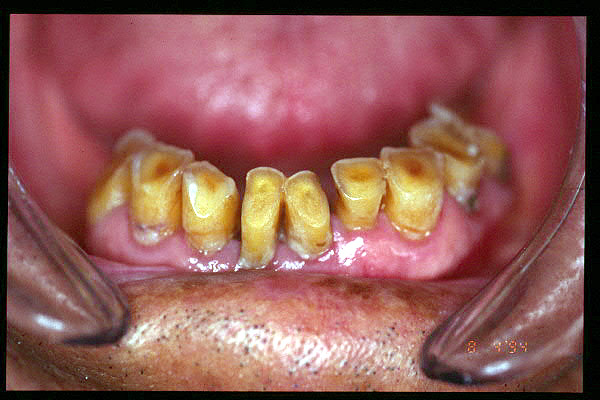

CM Desgaste por bruxismo, presencia de cálculo